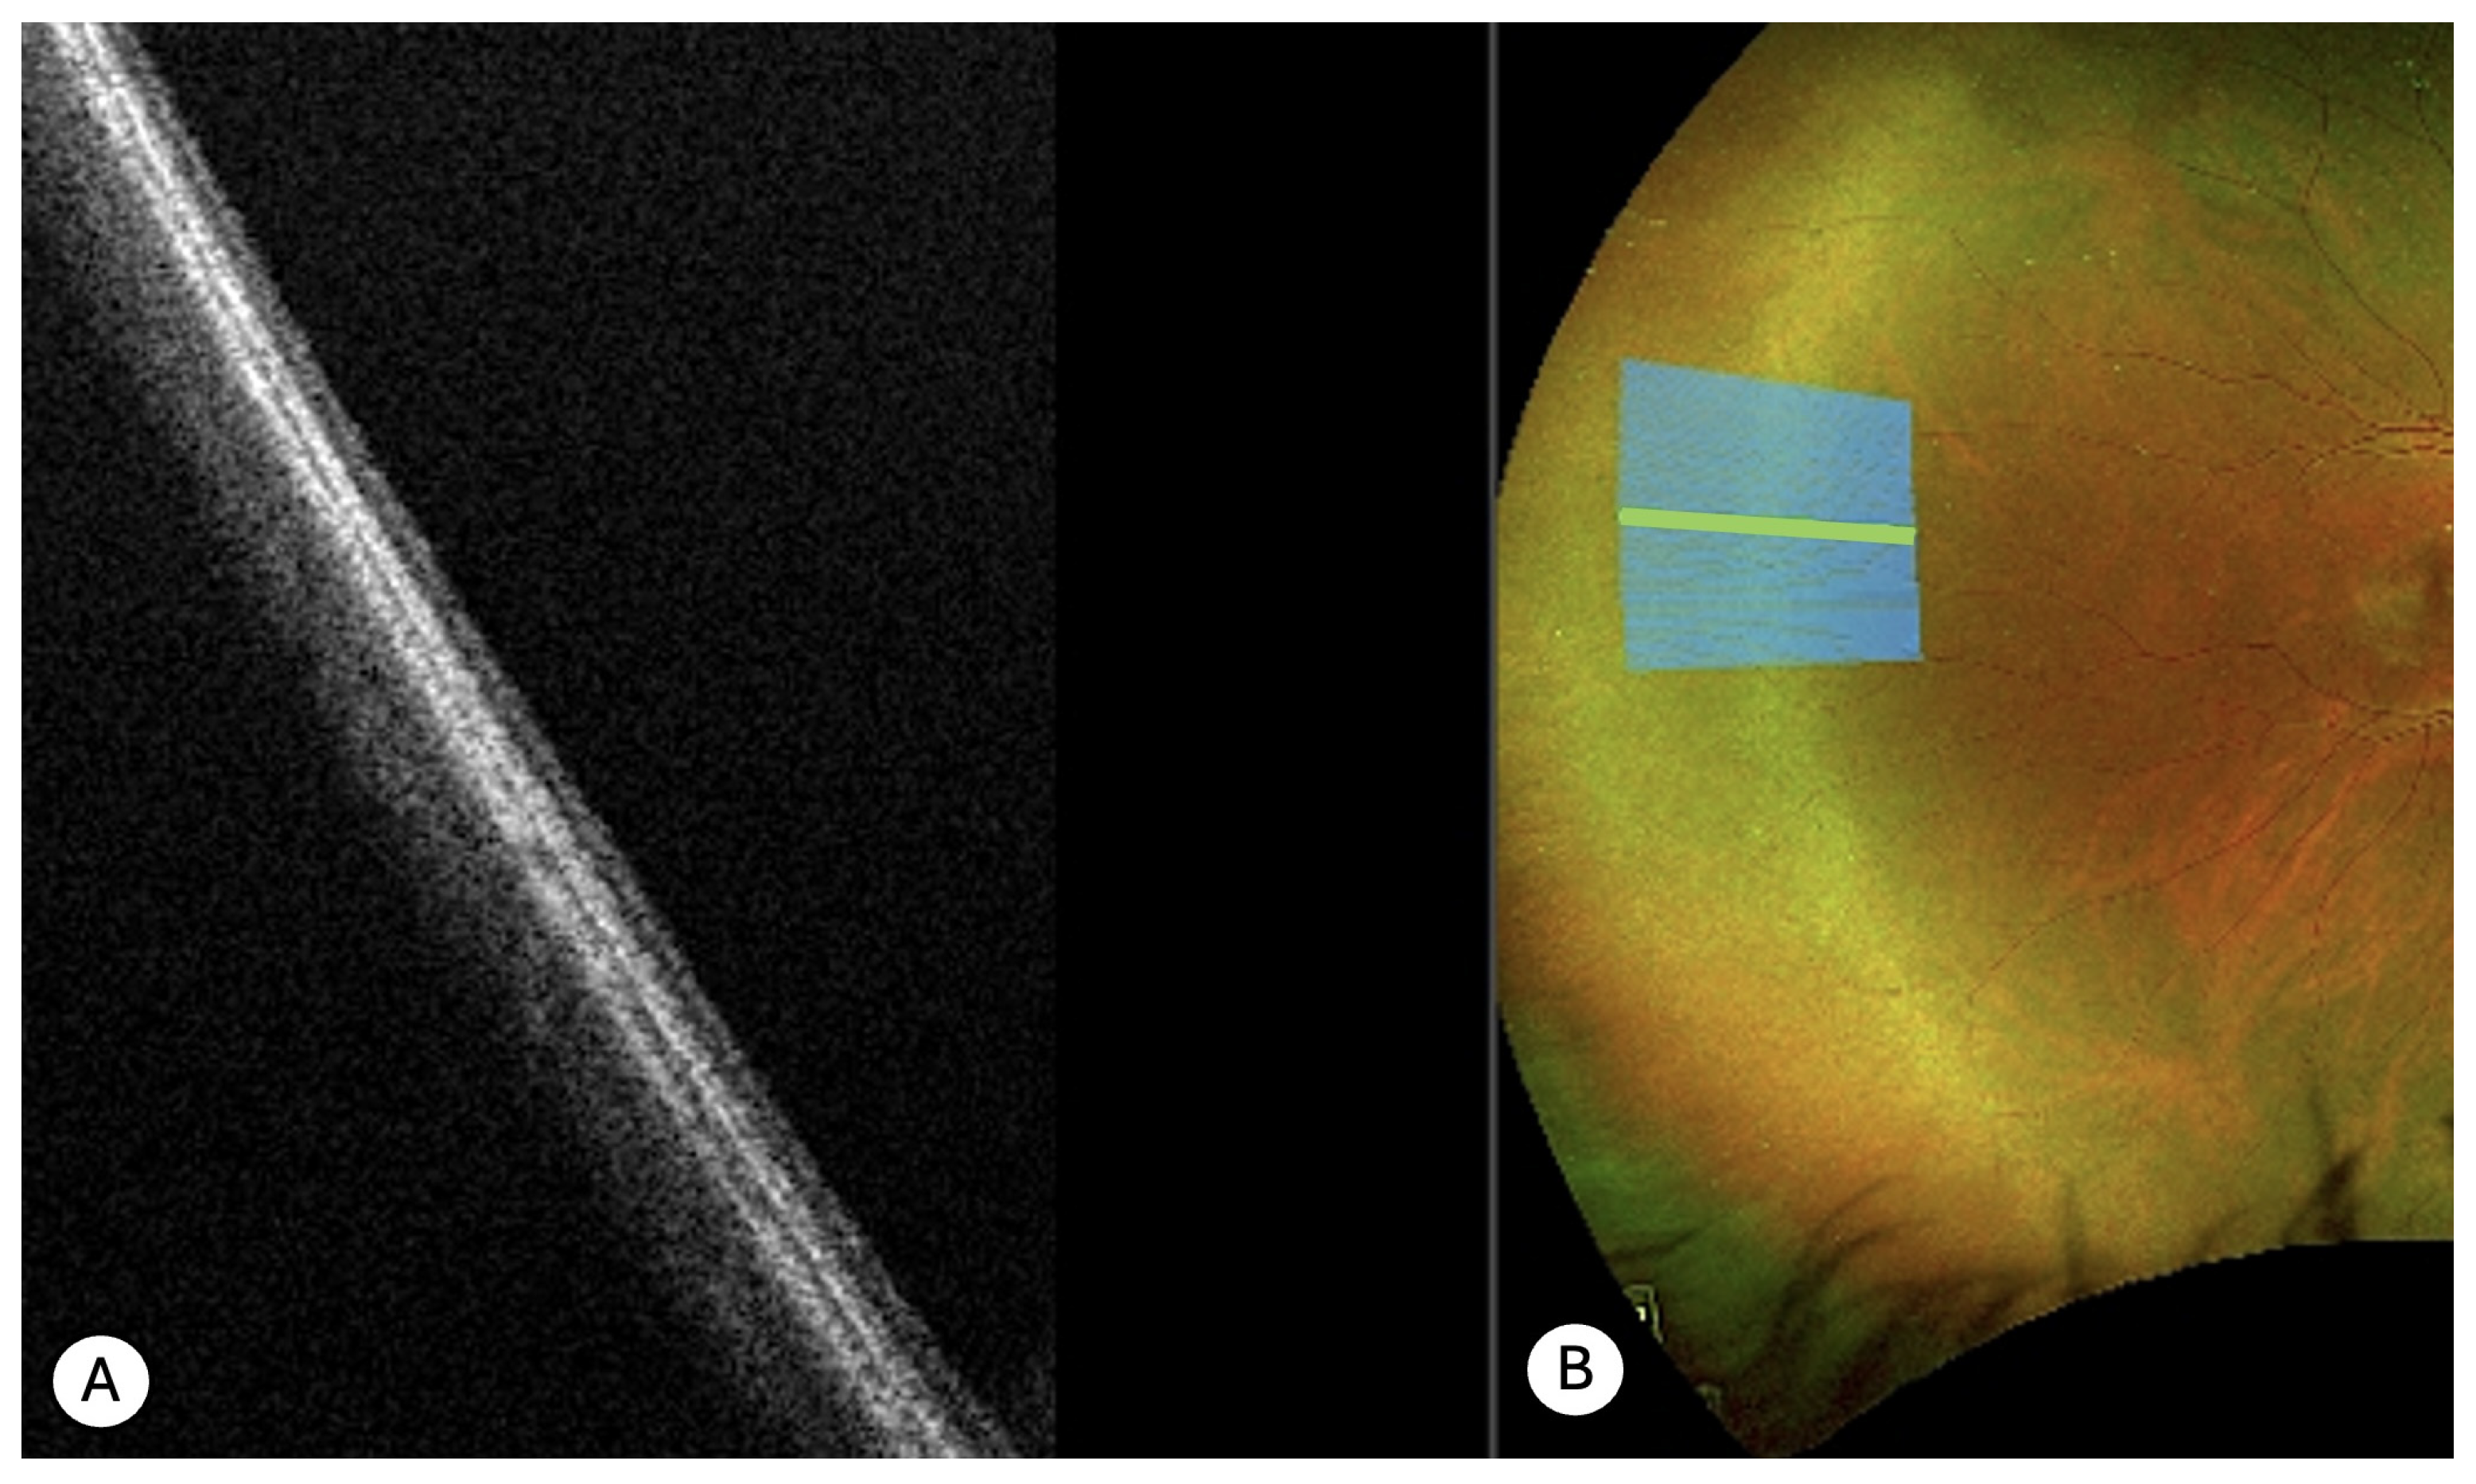

- Peripheral retinoschisis (N = 24)